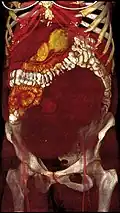

Giant leiomyomas almost filling the abdomen

-